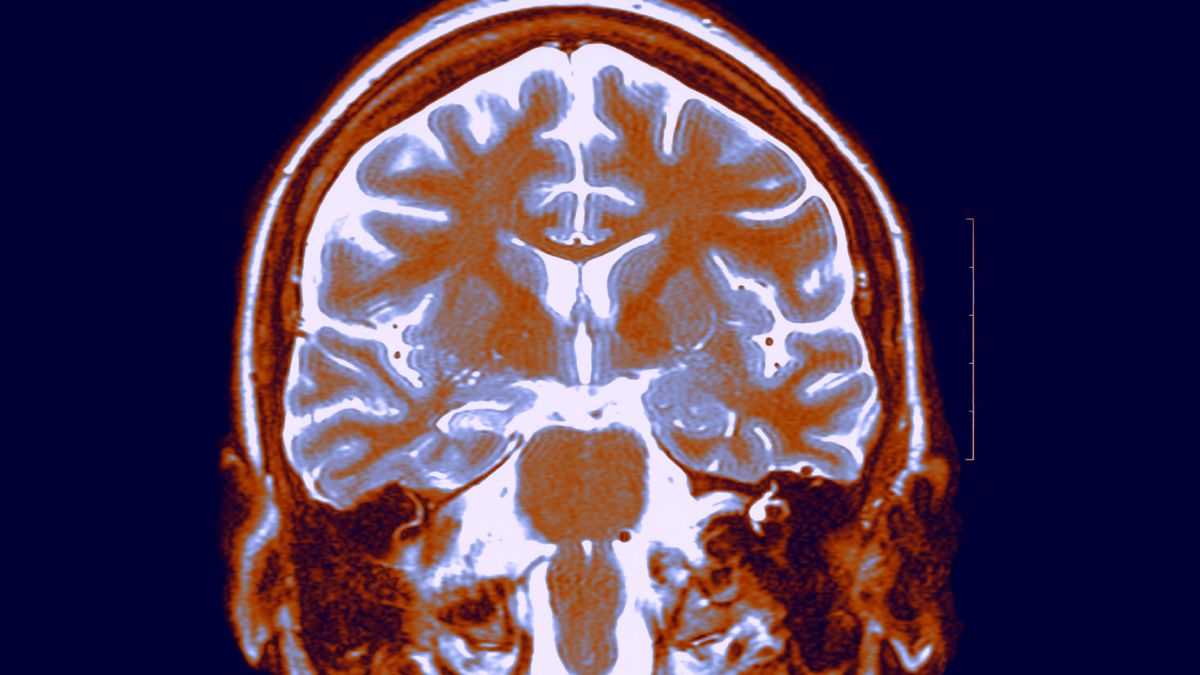

كشف باحثون من جامعة أوسلو - University of Oslo في دراسة واسعة النطاق، حللت أكثر من 12,600 فحص بالرنين المغناطيسي لحوالي 4,700 شخص سليم تتراوح أعمارهم بين 17 و95 عاما، أن أدمغة الرجال تتراجع بشكل أسرع وأكثر وضوحا في مناطق محددة مقارنة بالنساء.